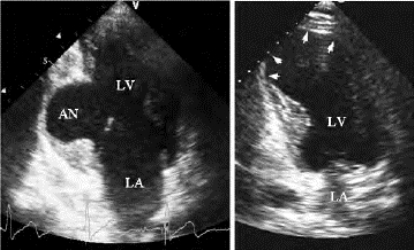

(1)左室壁与心包壁层之间有一囊状无回声腔,其壁为心包层(图19-15)。

(2)该腔与左室之间有一狭窄小孔相交通。

1.假性室壁瘤与左室的交通口小,真性室壁瘤与左室的交通口大。前者交通口径/瘤腔径≤0.5,后者交通口径/瘤腔径为0.9~1.0。

图19-15 假性室壁瘤二维超声(左图)和磁共振图像(右图)

左图:心尖四腔及心尖两腔切面二维声像图,显示左室心尖部室壁变薄、连续中断,其外侧心包腔内可见一囊性液区,其壁为心包壁和增生包裹的组织,与左室腔之间以一小孔相通。右图:磁共振长轴斜切面显示左室下壁基底部假性室壁瘤的瘤壁(大箭号)与心包(箭头)相连续,瘤腔内可见血栓(小箭号),破口最宽处(6.5cm)小于相应的瘤腔内径

2.假性室壁瘤瘤壁为心包层,无室壁结构,且与正常室壁心肌无连续性,真性室壁瘤瘤壁为变薄的室壁,巨大室壁瘤有时不易确定瘤壁肌性结构,呈菲薄的较强光带回声,但仍可见其与正常室壁延续。